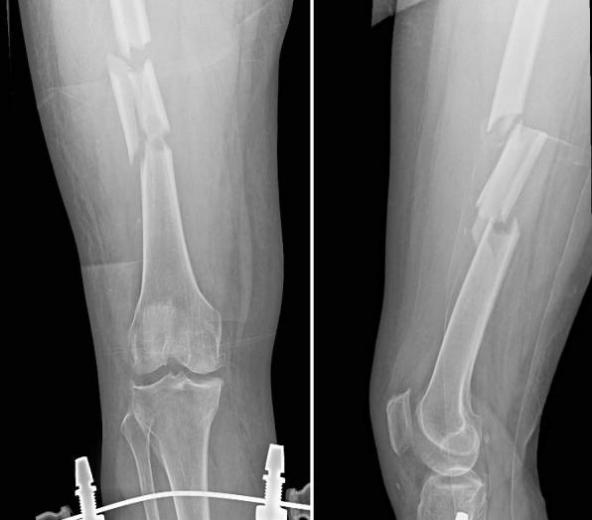

DR检查(数字化X射线摄影)

DR是传统X光片的升级版,其采用数字化技术,成像更清晰,检查更便捷。

【技术特点】

1.成像速度快:检查过程只需几分钟,适合急诊或大规模筛查。

2.辐射剂量低:DR的辐射量远低于CT,安全性较高。

3.二维平面图像:提供的是平面影像,适合观察骨骼、肺部等结构。

4.成本较低:检查费用相对便宜,适合常规体检。

【适用场景】

●骨折诊断:如四肢、脊柱、胸骨等部位的骨折。

●肺部疾病筛查:如肺炎、肺结核、肺气肿等。

●常规体检:如胸部X光片,用于初步筛查疾病。